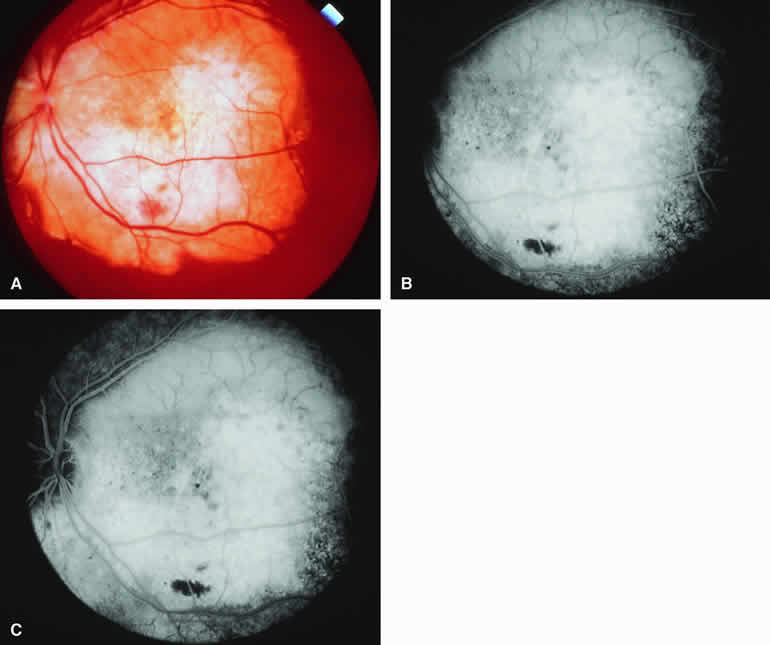

Fig. 18. Melanotic metastatic cutaneous melanoma to choroid and retina. A. Melanotic metastatic lesions to choroid (three lesions deep to retinal vasculature at left side of photograph) and retina (arcuate lesion in papillomacular distribution). B-D. Fluorescein angiogram of lesions. B. Laminar venous phase frame showing complete hypofluorescence of retinal lesion and patchy partial hypofluorescence corresponding to three choroidal lesions. C. Full venous phase frame showing persistent well-defined hypofluorescence of retinal lesion, slightly increased choroidal hypofluorescence corresponding to the two larger choroidal lesions, and almost no abnormality corresponding to the smallest choroidal lesion. D. Late-phase frame showing persistent nonfluorescence of the retinal lesion but no abnormality corresponding to the three choroidal lesions. (Courtesy of Michael Bourne, MD)

Melanotic Metastatic Choroidal Tumor (Metastatic Cutaneous Melanoma)

Occasional patients with metastasis from a primary cutaneous melanoma develop metastatic tumors in the choroid. If the metastatic choroidal lesions are darkly melanotic (see Fig. 18A), they will appear intensely hypofluorescent both early and late on fluorescence angiography (see Fig. 18B, C, and D). In contrast, if the lesions are relatively hypomelanotic, they may exhibit only mild relative hypofluorescence early. Most hypomelanotic metastatic melanomas to the choroid appear relatively hyperfluorescent on late frames of fluorescein angiograms because of progressive fluorescein leakage during the course of the study.